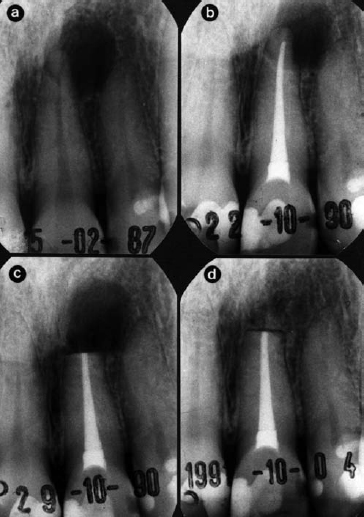

Fig 2. Radiographs of left maxillary central incisor followed over >4.5 year period. A radiolucent lesion was present (a), which was managed by endodontic treatment. The tooth was followed-up over 44 months with no signs of healing (b), so periapical surgery was performed (c) and 1 year later there is complete bone repair (d). Histopathological analysis of the surgical specimen revealed a cyst filled with cholesterol crystals. No bacteria were detected in the root apex or lesion. Reprinted with permission from Nair.142

The reasons for disease persistence in well-treated root-filled teeth have been poorly characterized until a series of studies published during the 1990s.4346 Using block biopsy material from non-healed periapical tissues including apices of the root-filled teeth, analysis by correlative light and electron microscopy showed that there were four factors that may have contributed to persistence of a periapical radiolucency after treatment (Fig 2). The factors were: (i) intraradicular infection;43 (ii) extraradicular infection by bacteria of the species Actinomyces israelii and Propionibacterium propionicum;4749 (iii) foreign body reaction;44,50 (iv) cysts, especially those containing cholesterol crystals.45